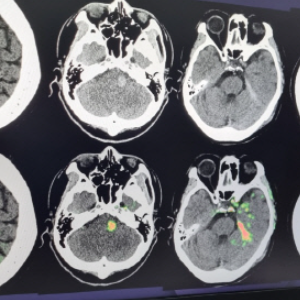

딥노이드는 국내에서 의료영상 분석 기술을 가장 빠르게 상용화한 기업 중 하나로, 병원에서 발생하는 대규모 영상 데이터를 바탕으로 정확하고 효율적인 진단을 지원하는 AI 솔루션을 제공합니다. 특히 주목할 부분은 2025년 상반기 중 국내 최초의 생성형 AI 기반 의료 소프트웨어 출시를 예고하고 있다는 점입니다. 이는 기존 AI 시스템을 넘어서 의사의 판단을 보조하는 것을 넘어, 스스로 판단 가능한 의료 보조 생성 시스템을 의미합니다. 현재 딥노이드는 이 기술을 적용한 AI 내시경 솔루션, 폐 질환 판독 AI, 뇌출혈 자동 분석 AI 등을 다수 개발 중이며, 의료 현장에서의 직접 활용성과 신뢰성을 높이는 데 집중하고 있습니다. 이처럼 기술의 진보성과 적용 분야의 다양성은 딥노이드를 생성형 의료 AI 관련주 대장주 반열에 올려놓기에 충분합니다.